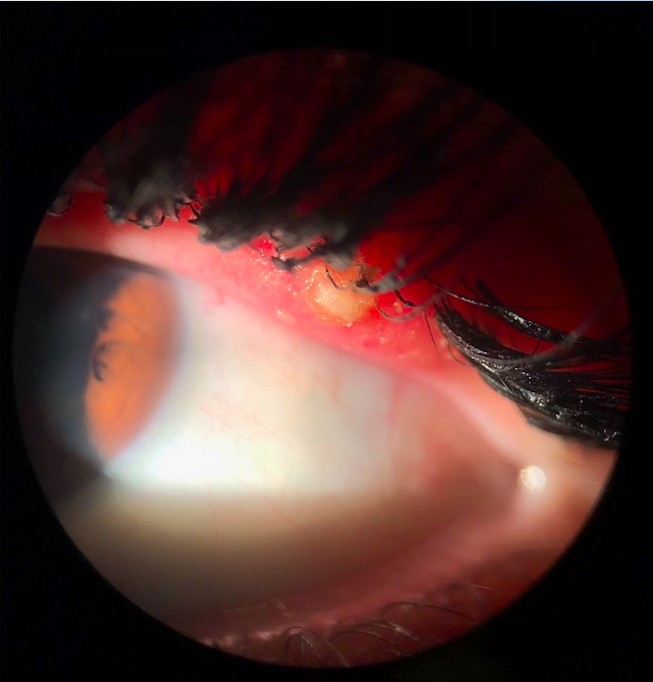

The popular cosmetic trends in today’s world including eyelash curling, brow tinting, tubing mascara, and more!

Ocular complications secondary to some dangerous ingredients in many products